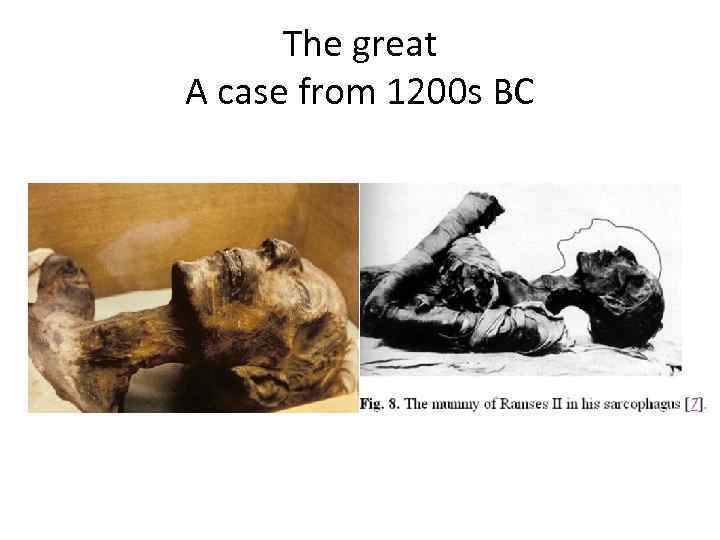

The great A case from 1200 s BC

The great A case from 1200 s BC